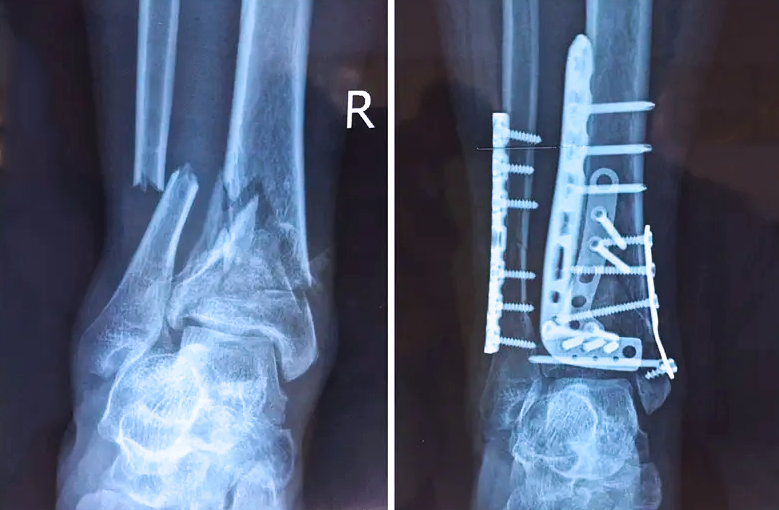

對(duì)于骨科醫(yī)生而言,關(guān)節(jié)外的骨折是相對(duì)比較簡(jiǎn)單的,因?yàn)殛P(guān)節(jié)外的骨折允許我們復(fù)位的時(shí)候有一些偏差,但是如果骨折部位在關(guān)節(jié)內(nèi),我們就不能有任何的偏差。而且關(guān)節(jié)內(nèi)的骨折是有關(guān)節(jié)面的,如果關(guān)節(jié)面不平整,就會(huì)導(dǎo)致患者以后出現(xiàn)創(chuàng)傷性關(guān)節(jié)炎等癥狀,或者出現(xiàn)長(zhǎng)期的疼痛,甚至造成殘疾。所以對(duì)于關(guān)節(jié)內(nèi)的骨折,一定要做到“解剖復(fù)位”,就像搭積木一樣,每個(gè)積木塊、每個(gè)碎骨塊都要完好的拼到一起,做到嚴(yán)絲合縫。

踝關(guān)節(jié)是人體中負(fù)重較大的關(guān)節(jié),也是活動(dòng)度較大的地方,所以對(duì)于足踝部位的關(guān)節(jié)內(nèi)骨折,我們更需要做到“解剖復(fù)位”。對(duì)于這種關(guān)節(jié)內(nèi)的骨折,尤其是踝關(guān)節(jié)內(nèi)部的骨折,不僅需要進(jìn)行X影像平片正側(cè)位的拍攝,由于在二維影像上無(wú)法判斷關(guān)節(jié)面的受損情況,往往還需要進(jìn)行三維影像的檢查。

在術(shù)前,我們需要做三維掃描的CT檢查,我們必須要有CT的片子,還要有三維的重建。

在術(shù)中,我們?cè)趺慈ヅ袛嚓P(guān)節(jié)面平不平整呢?常規(guī)的正側(cè)位影像是不能判斷的。有些醫(yī)生為了準(zhǔn)確的判斷,可能會(huì)選擇做開(kāi)放性的手術(shù),把關(guān)節(jié)暴露出來(lái),在眼睛的直視下判斷關(guān)節(jié)面平不平整。但是關(guān)節(jié)全部打開(kāi),無(wú)疑增加了病人的創(chuàng)傷,而且增加了患者的恢復(fù)時(shí)間。所以如果在術(shù)中我們有三維影像的支持,對(duì)醫(yī)生做手術(shù)而言就會(huì)事半功倍,而且能夠大大的增加手術(shù)準(zhǔn)確度,增加患者術(shù)后的預(yù)后。所以在術(shù)中有三維影像的支持是非常必要的!